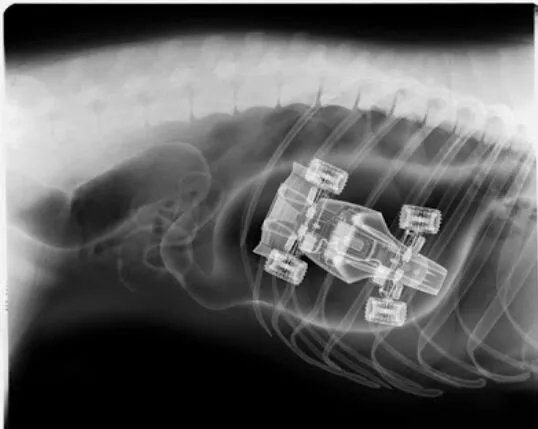

这是一堆杂草线团之类的异物。

这些都是在狗狗的胃里发现的,拍的X光图,看到那把刀在狗狗胃里,心里不紧张吗不担心 ,万一你家的狗狗也吃下去,想都不敢想!

狗狗似乎总是无法控制自己去吃一些没有营养价值的东西。针线、木勺、硬果壳、果核、塑料袋、珠宝、石块、抹布和袜子都有可能吃下去,狗狗胃内长期滞留这些异物不能被胃液消化,会造成胃黏膜损伤,影响胃功能。